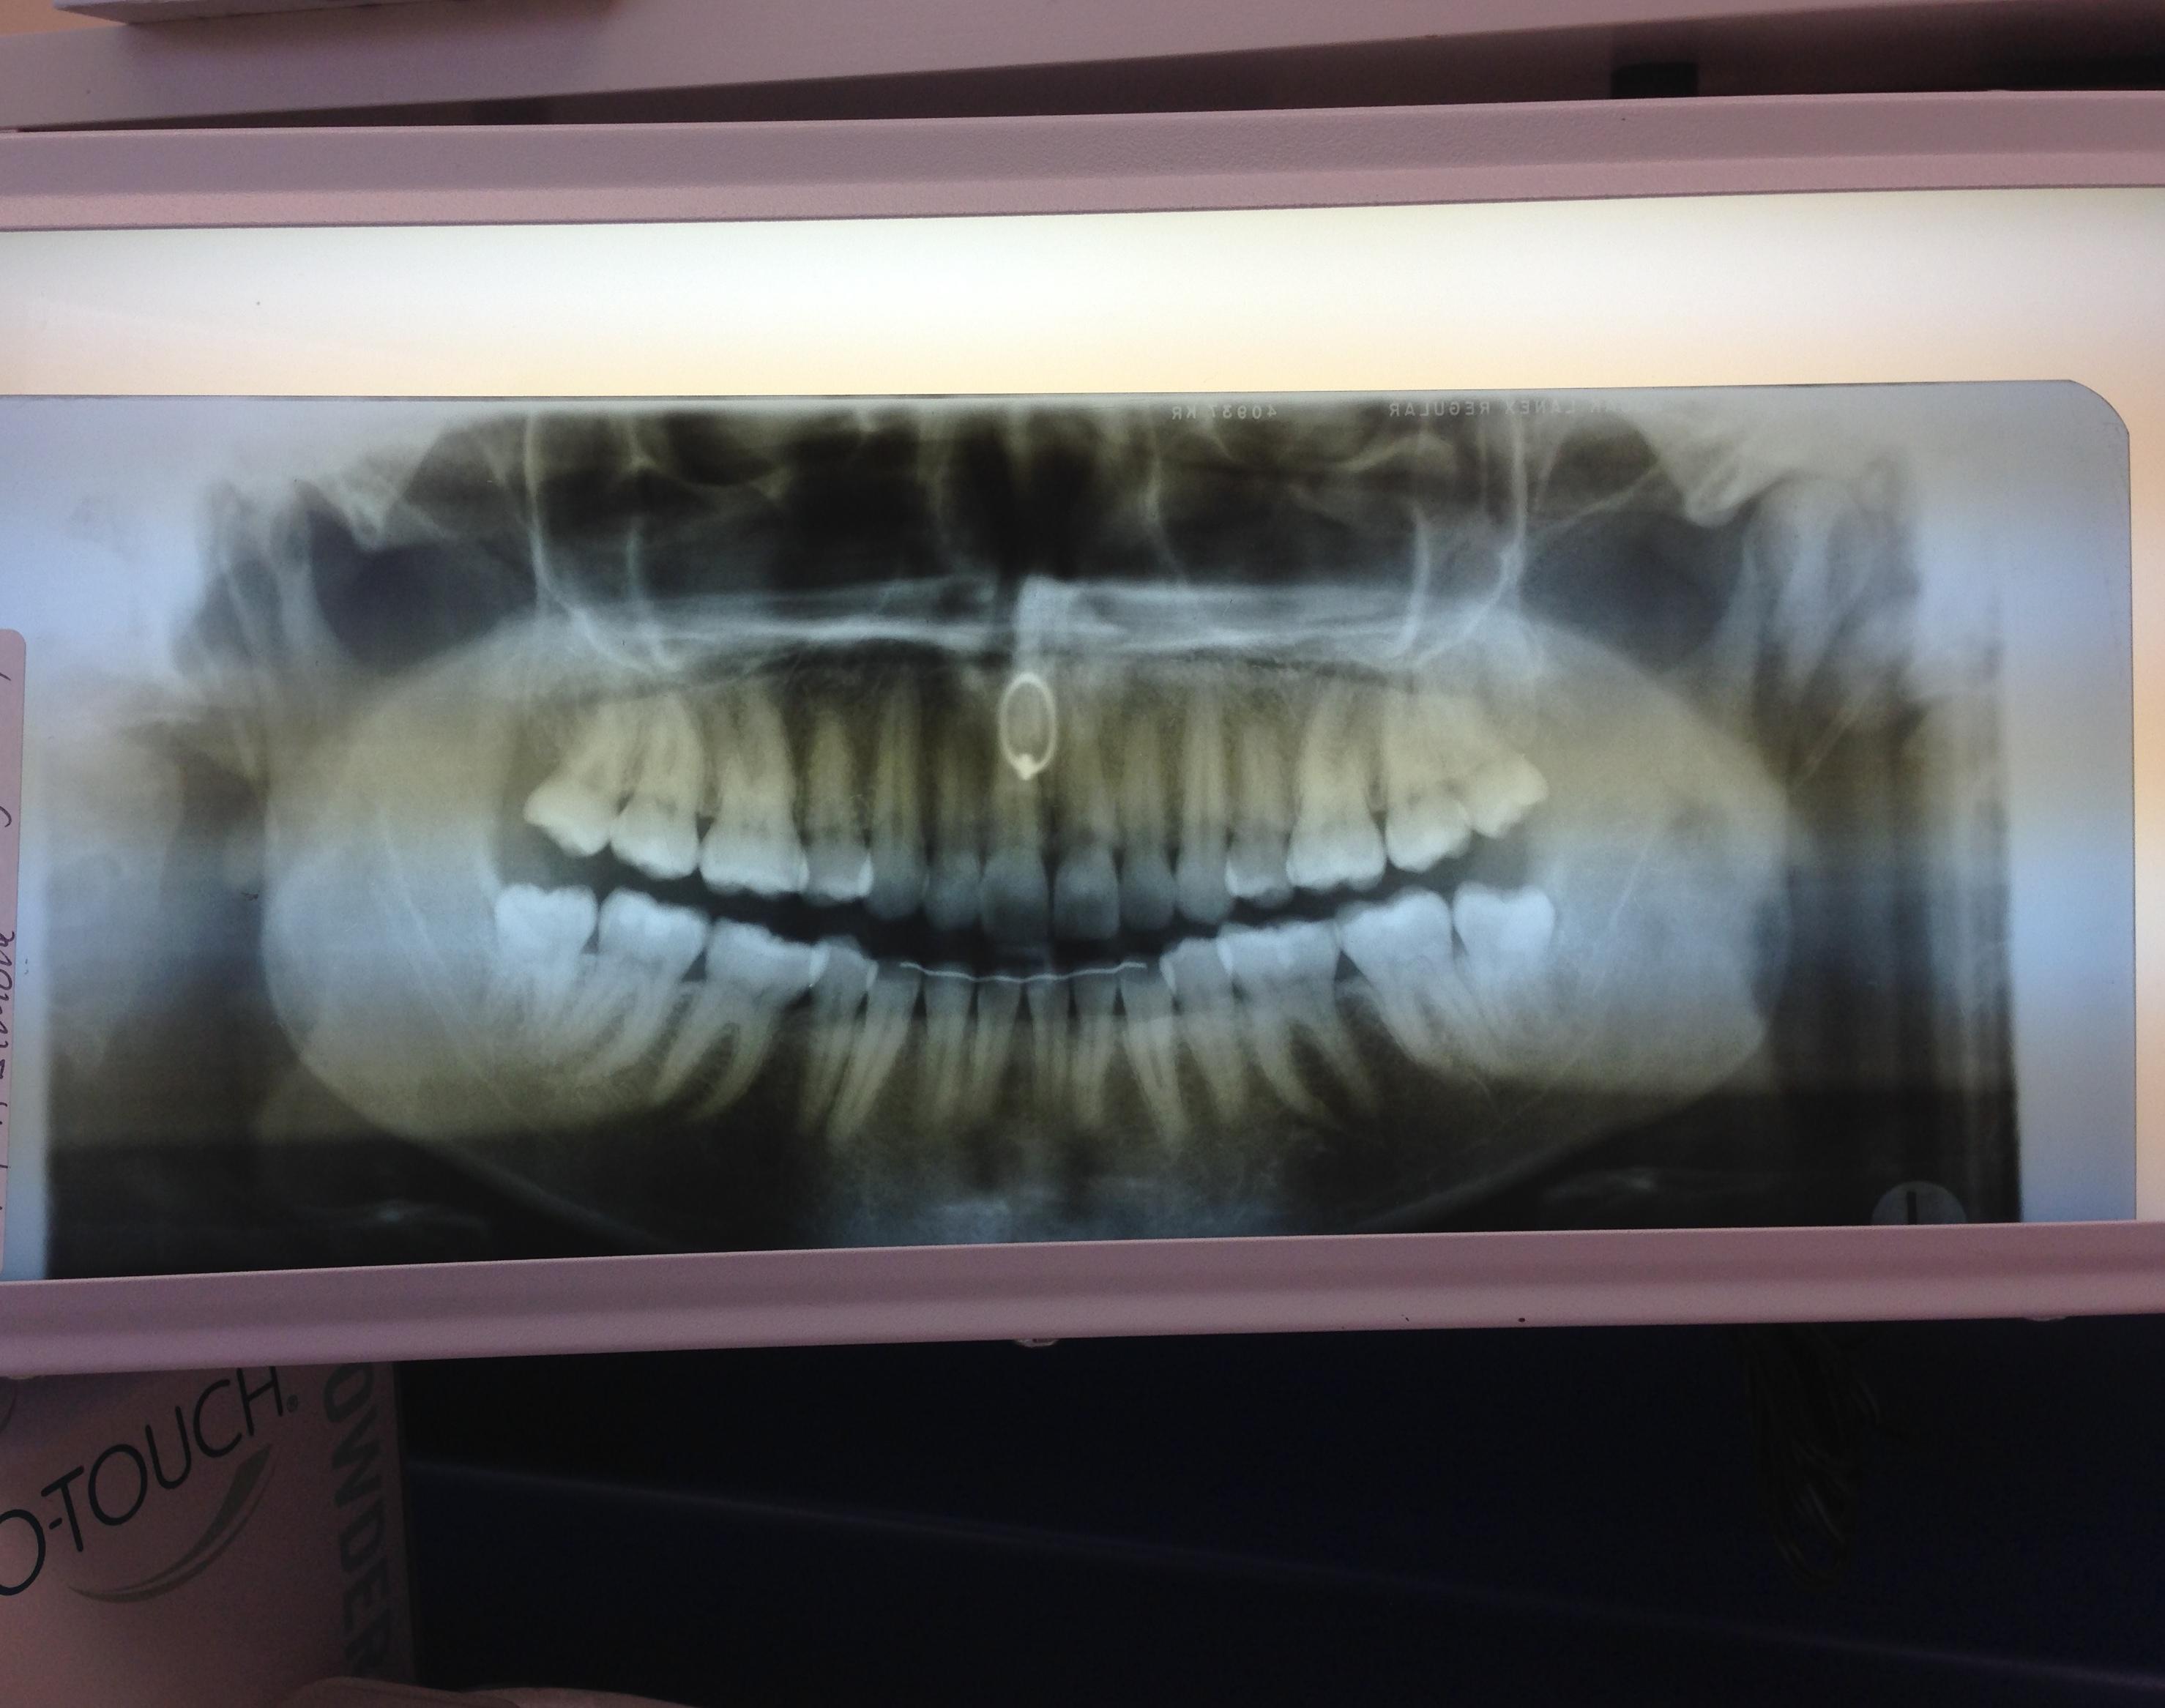

Got an X ray at the dentist and couldn’t take out my nose ring, so now Nose Ring Dental X Ray However its up to the clinician to. The nose ring will appear on the xray in an area that can block a possible tooth image. For intra oral ones then they can be left in. As for record keeping, a dentist may. For extra oral they ideally should be taken out but. Contact us for costs and all types of. Nose Ring Dental X Ray.

Was told I could keep my nose ring on during xrays... Got a laugh out Nose Ring Dental X Ray For extra oral they ideally should be taken out but. The nose ring will appear on the xray in an area that can block a possible tooth image. Contact us for costs and all types of x. As for record keeping, a dentist may. However its up to the clinician to. For intra oral ones then they can be left. Nose Ring Dental X Ray.